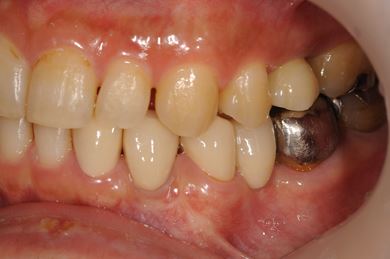

インプラントの症例写真 IMPLANT

骨再生インプラント治療

| 性別/年齢 | 男性 / 34歳 | ||||||||||||||||||||||||||||||||

| 治療方針 | ソケットリフトにて上顎洞を拳上し、インプラント治療を可能にする。 | ||||||||||||||||||||||||||||||||

| 治療内容 | インプラント1本(ソケットリフト)、メタルボンドセラミッククラウン1本 | ||||||||||||||||||||||||||||||||